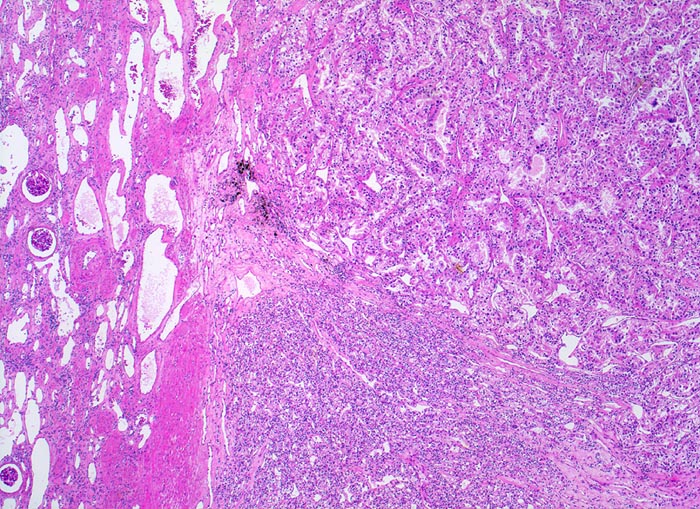

PathoPic – image database / PathoPic ID 4888 - hellzelliges Nierenzellkarzinom

hellzelliges Nierenzellkarzinom

Die Grenze zwischen Karzinom und Nierenparenchym ist scharf und enthält zahlreiche erweiterte Gefässe. Das Karzinom bildet im oberen Anteil drüsige Strukturen, der untere Anteil erscheint solide.

Hellzellige Nierenzellkarzinome zeigen ein expansiv verdrängendes Wachstum an der Tumorinvasionsfront.